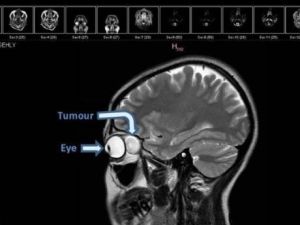

The patient was discharged the following day, with her vision fully restored. (File photo)

November 22nd, 2016 - 08:44 GMT

Dubai doctor removes freakishly huge tumor from behind woman’s eye